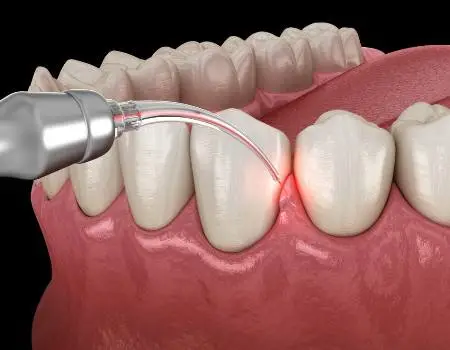

لیزر درمان پریودنتال مجموعهای از تکنیکهای کمتهاجمی است که با انرژی لیزر روی بافت نرم و گاه سخت ناحیه پریودنتال اعمال میشود تا بار میکروبی پاکتها کاهش یابد، بافتهای بیمار هدف قرار گیرد، خونریزی کنترل شود و ترمیم بافتی بهبود یابد. در سالهای اخیر، فناوری لیزر بهصورت گستردهتری در کنار درمانهای استاندارد (مانند SRP، جراحی فلپ، بازسازی استخوان و …) بهکار میرود و بسته به مورد، میتواند به کاهش عمق پاکت، بهبود خونریزی حین پروبینگ و راحتی بیمار کمک کند. مرورهای جدیدتر (تا ۲۰۲۵) نیز مزایای بالقوهای مثل اثر ضدباکتریایی، برداشت بیوفیلم و احتمالا اثرات فتوبیومادولیشن را گزارش کردهاند؛ هرچند همچنان تاکید دارند پروتکل باید مبتنی بر شواهد و در کنار درمانهای مکانیکی باشد.

کار با لیزر بر اساس پروتکل: هدایت فیبر/هندپیس بهصورت کنترلشده در پاکتها، کاهش خونریزی و کاهش بار میکروبی.

ایجاد شرایط ترمیمی بهتر: بافتهای بیمار برداشته/کوآگوله میشود تا شرایط چسبندگی بهتر فراهم گردد.

در پاکتهای عمیق یا مناطقی که دسترسی مکانیکی محدود است، لیزر میتواند به حذف بیوفیلم و باکتریها کمک کند. مثال: با استفاده از لیزر «Er :YAG» یا «Nd :YAG» طیفی از مطالعات گزارش کردهاند کاهش عمق پاکت (PPD) و بهبود اتصال کلینیکی (CAL) را. PMC